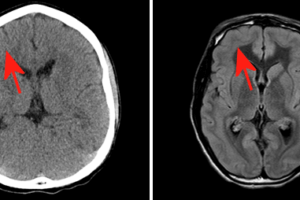

Band Heterotopia

Band heterotopia is a congenital disorder that results from the disrupted migration of neurons. Neurons originate in the germinal matrix adjacent to the ventricules and ultimately migrate outward to form the grey... Read more »